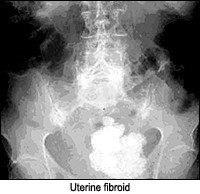

- cloud-like.

Rim-like appearance can be described as a wall of calcification surrounding a hollow structure, as in a renal cyst. Track-like or linear calcification indicates a tubular structure, as in the walls of the ureters or arterial walls. Lamellar calcification is formed in the lumen of a hollow structure, as in renal stones or stones in the gallbladder. Cloud-like calcifications are formed in a solid organ or tumor, such as a leiomyomas of the uterus or calcifications in the pancreas. Once the appearance of the calcification is apparent, the next step is to consider what anatomical structure is in that location. I am assuming one has ruled out the possibility of an artifact before considering a calcification as such.

The following images are representative of the four classic appearances of calcifications (rim-like, linear, lamellar, and cloud-like):

Calcifications in uterine fibroids appear as a collection of berries and generally are not difficult to differentiate from other calcifications in the pelvis.